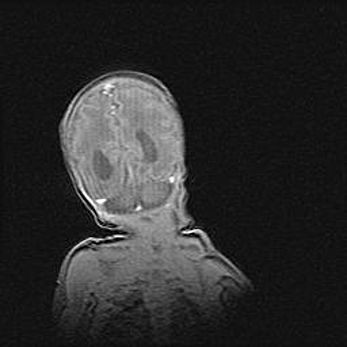

Открытая гидроцефалия.

Возраст: 9 месяцев 12 дней

Вес: 6800 г

Пол: мужской

Окружность головы: 41,5 см

Срок гестации: 28 недель

Гидроцефалия головного мозга у новорожденных имеет характерный признак: опережающий рост окружности головы приводит к визуально хорошо определяемой гидроцефальной форме сильно увеличенного в объёме черепа. Детские неврологи определяют следующие симптомы гидроцефалии у грудничков: выбухающий напряжённый родничок, частое запрокидывание головы, смещение глазных яблок к низу.